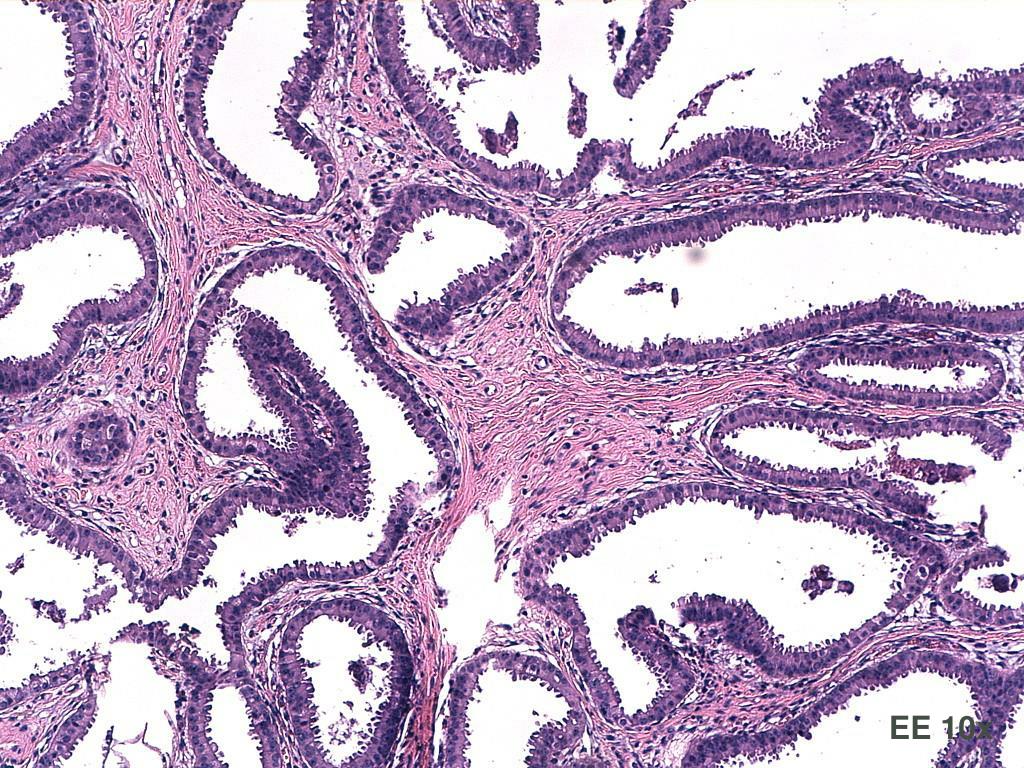

2. L.D., 50 anni,microcalcificazioni QIE dx

3. EE 10x EE 10x

10. DIAGNOSI. Parenchima mammario con focolai di iperplasia dutto-lobulare a fisionomia apocrina con lieve atipia e necrosi intraduttale, associata a calcificazioni grossolane. Focale, puntiforme e irregolare positività per proteina p63, proteina 100 e actina 1A4. DIN1b/DIN1c (IDA/DCIS BG)